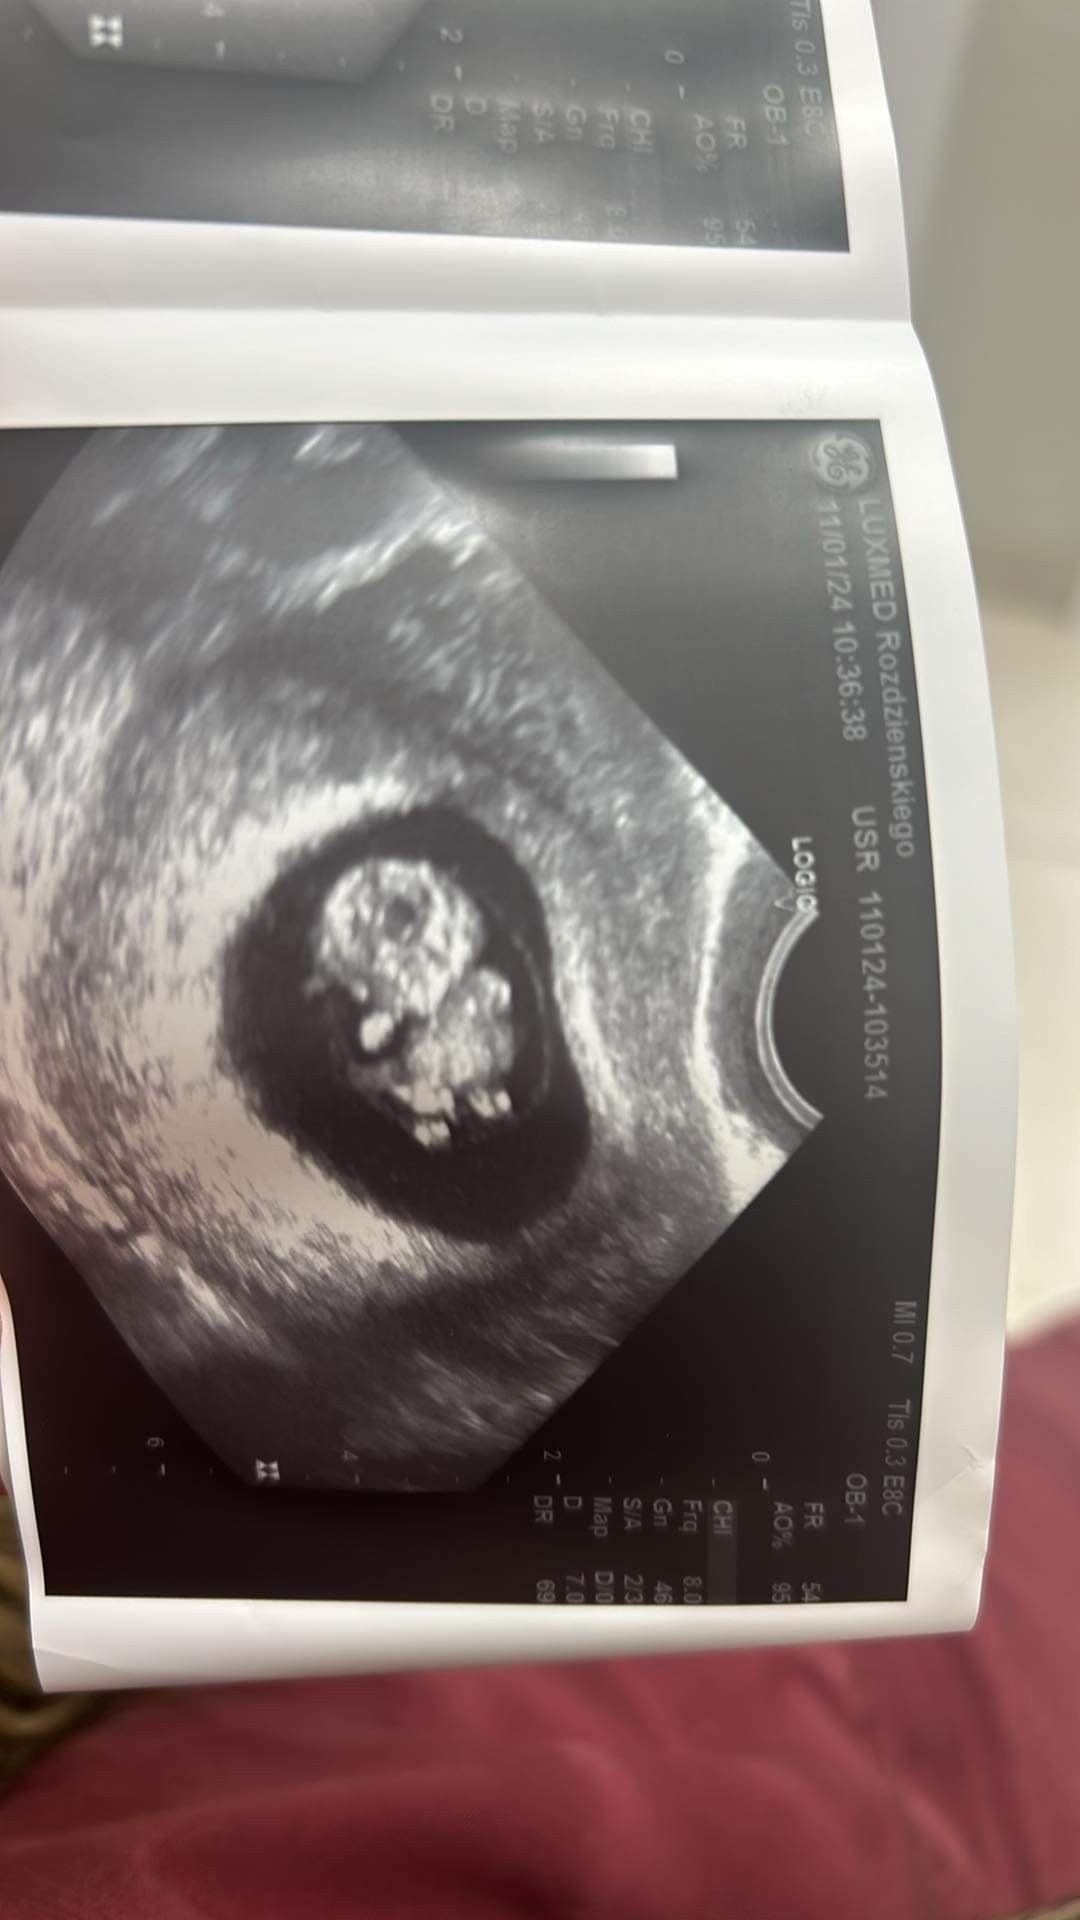

udało się! Chyba wszystkim kciuki drętwiałyJest zarodek z bijącym serduszkiem!!aż nie mogę w to uwierzyć. Ciąża jest młodsza niż z OM, termin po tym USG wyliczyła na 3 września, ale pozwólcie, że zostanę z Wami

stres mnie pewnie nie opuści za szybko. Kolejna wizyta na NFZ dopiero 8.02

omgf !!!!! co za wiadomośc!!!! cudownie!!!Jest zarodek z bijącym serduszkiem!!aż nie mogę w to uwierzyć. Ciąża jest młodsza niż z OM, termin po tym USG wyliczyła na 3 września, ale pozwólcie, że zostanę z Wami